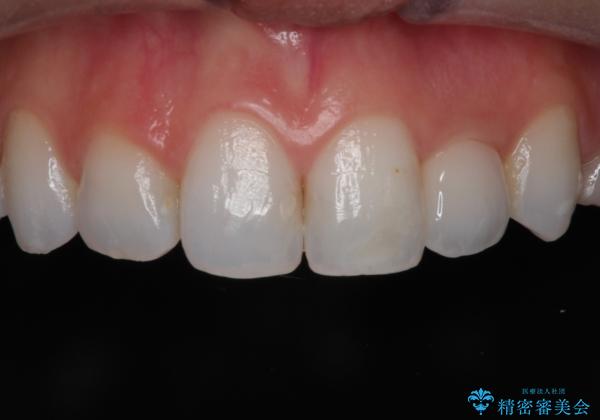

前歯の被せ物をやり替えたい

- 以前に被せ物の治療した箇所に汚れが溜まりやすいことを主訴に来院されました。

矯正治療を行なったのち、オールセラミッククラウンにて修復しております。

矯正治療はインビザラインで行なっております。